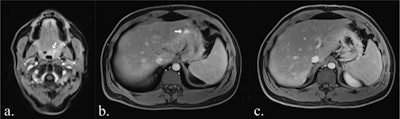

Sequences included in the study MRI protocol: (a) coronal TIRM (turbo inversion recovery magnitude) sequence, (b) coronal T1-weighted sequence, (c) axial FLAIR (fluid-attenuated inversion recovery) sequence (head only), (d) axial T2-weighted fast spin-echo sequence (HASTE), (e) axial diffusion-weighted imaging (b-value 900), (f) an axial ADC map, (g) axial T1-Dixon water-only images before contrast agent, and (h) after administration of contrast agent.All figures courtesy of Dr. Myriam Keymling et al and European Radiology